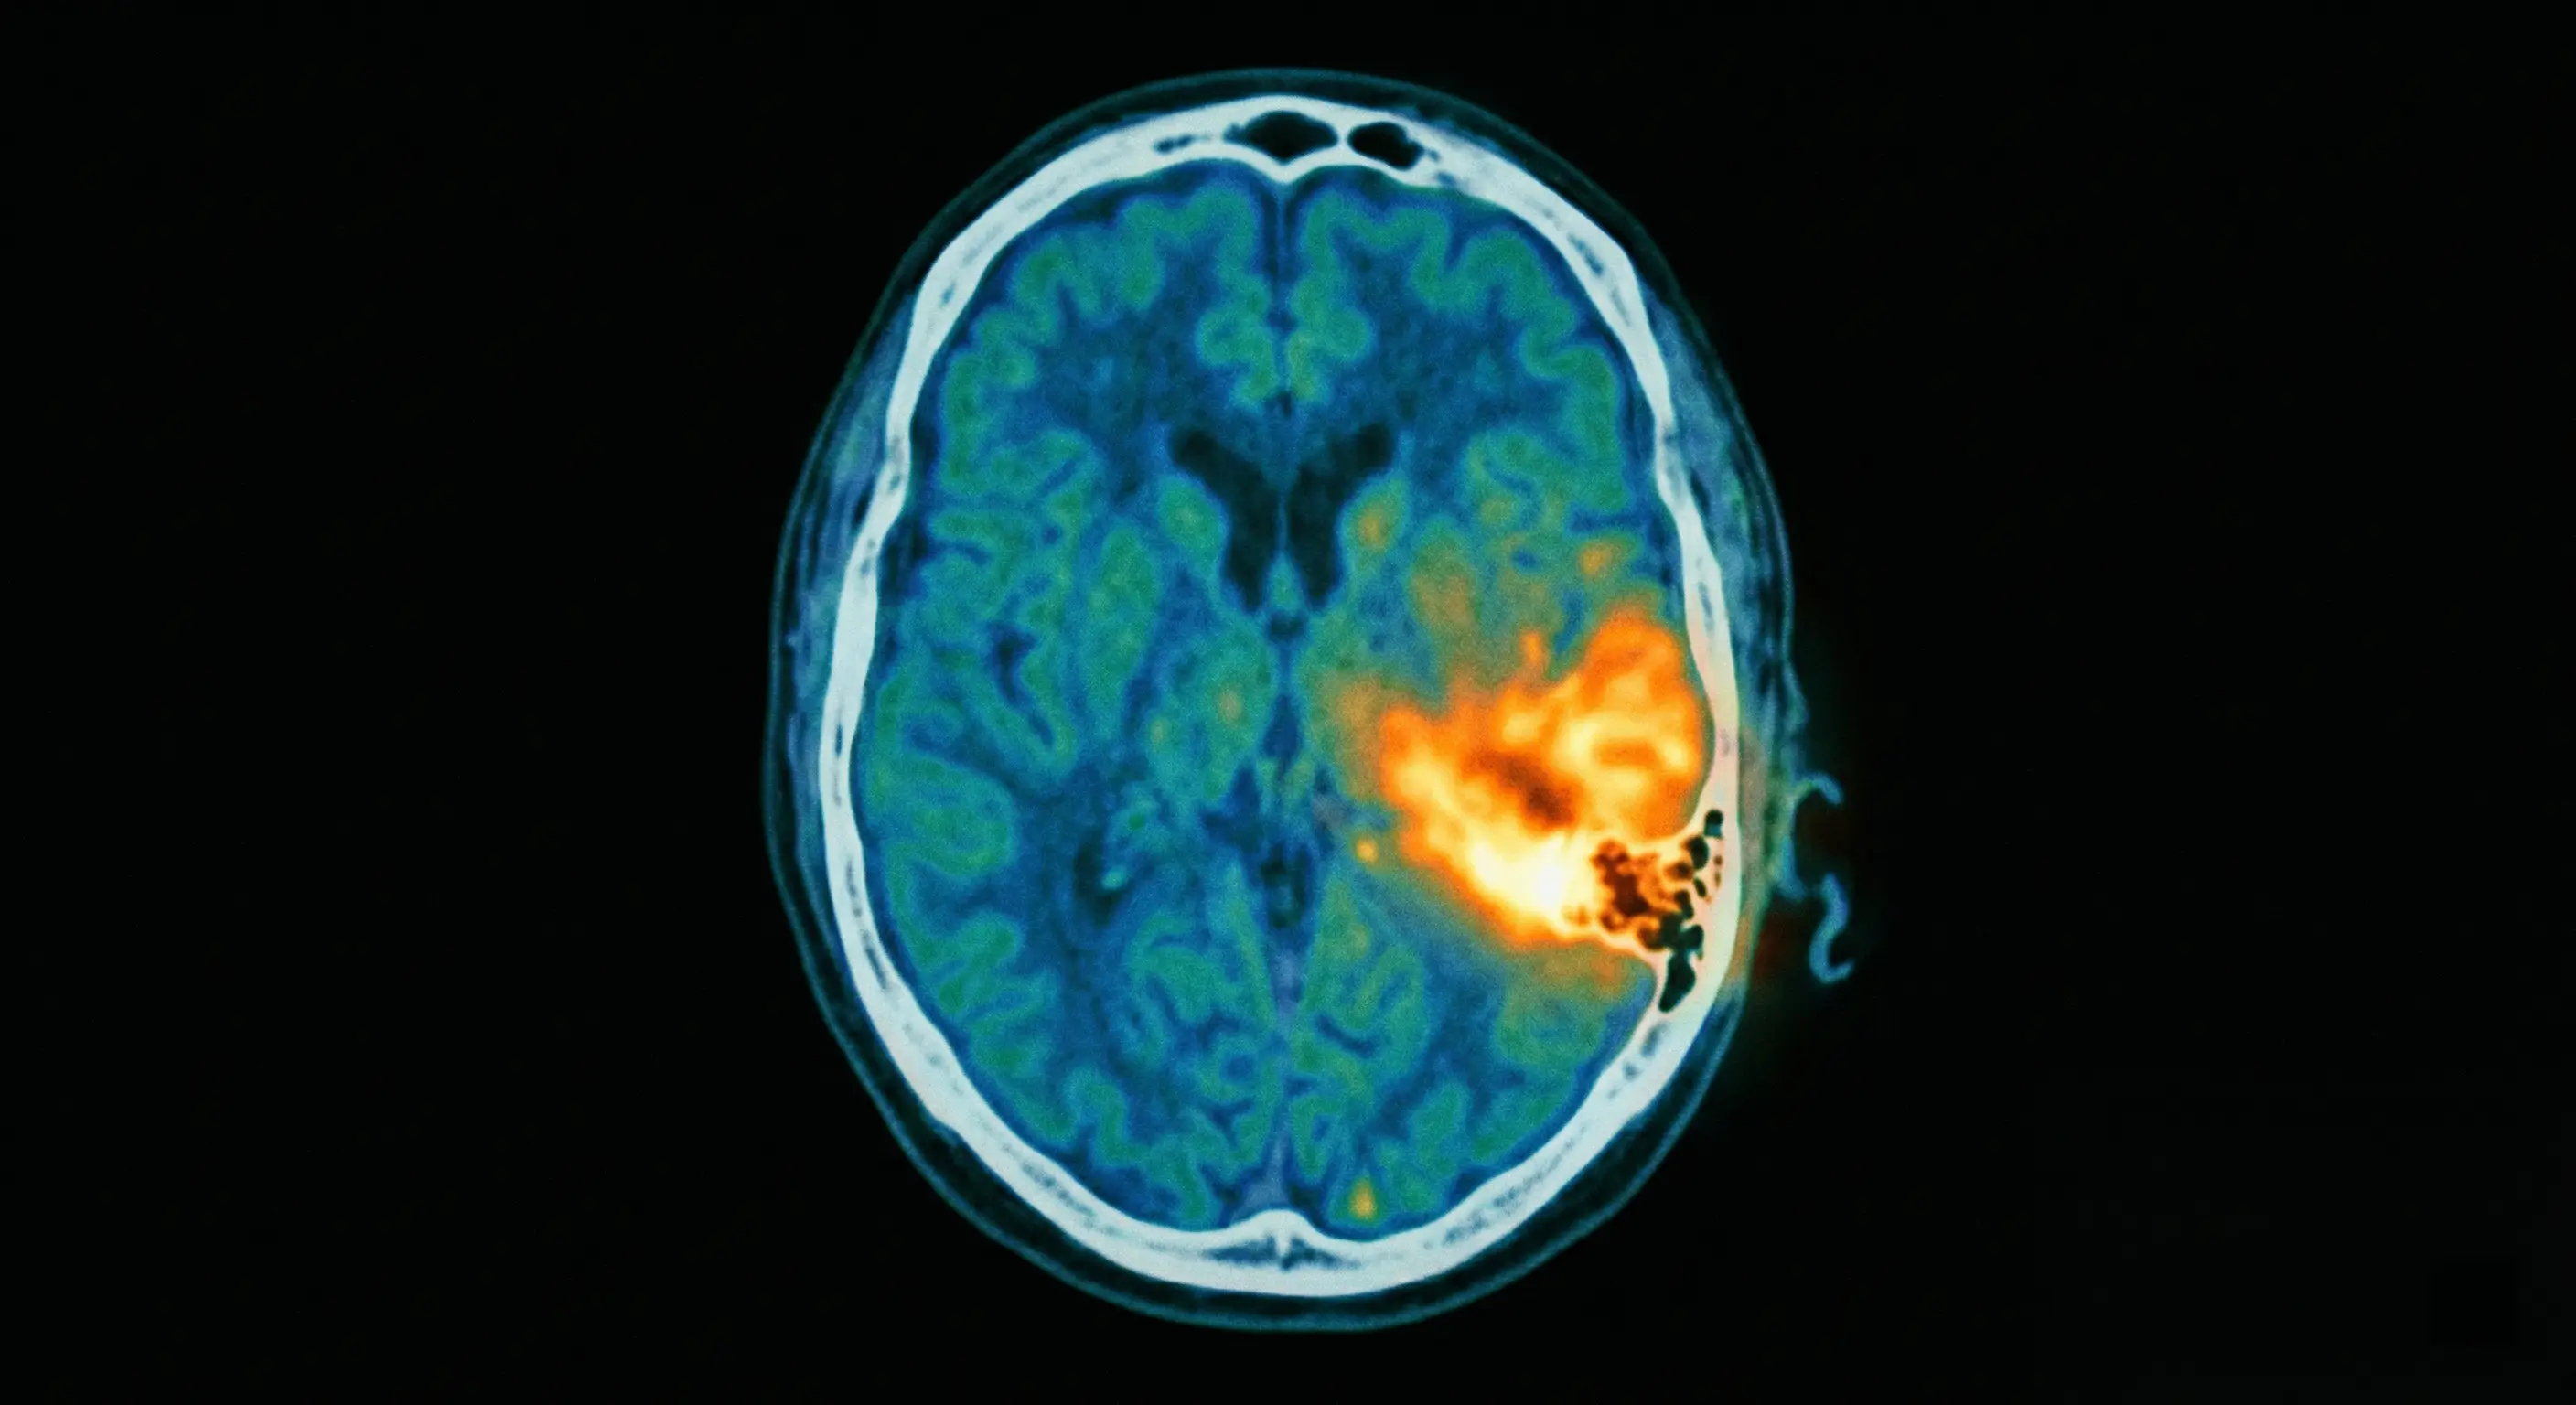

- Diagnostic : le scanner (TDM) des rochers est l’examen de référence pour évaluer l’érosion osseuse.

L’examen de référence demeure le scanner (TDM) des rochers. Ce procédé permet de visualiser avec précision l’atteinte de l’os temporal. Il évalue aussi l’étendue des lésions osseuses.

L’IRM ou la scintigraphie complètent parfois le bilan initial. Ces outils facilitent la surveillance de la cicatrisation osseuse. Le suivi s’étale généralement sur plusieurs mois.

Le diagnostic repose sur des examens de précision, notamment le scanner (TDM) des rochers, qui permet d’évaluer l’érosion de l’os temporal. Une mise en culture des sécrétions de l’oreille est aussi systématiquement réalisée pour identifier précisément la bactérie responsable et adapter les antibiotiques.